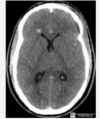

Perfectly

Hemorragia intraparenquimatosa?